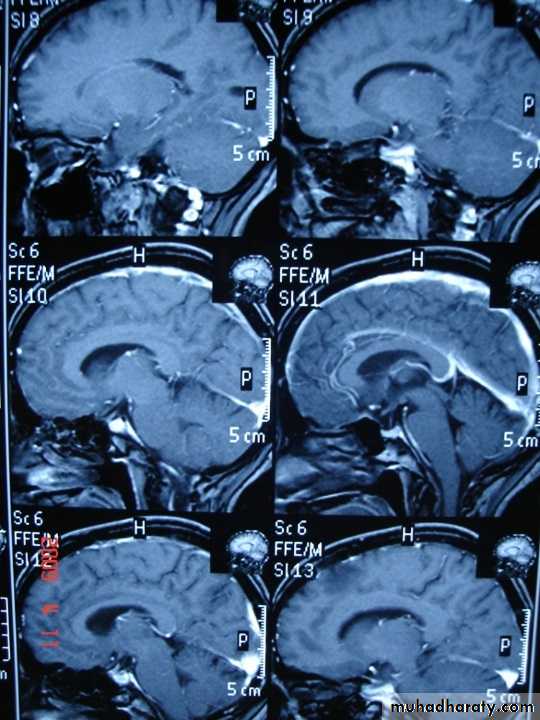

Sagital section of brain ( T1 w post contrast injection)

T 2/ FLAIR SEQUENCE: fluid attenuation inversion recoveryT 1w + GADOLINEUM INJECTION / SAGITAL SECTION